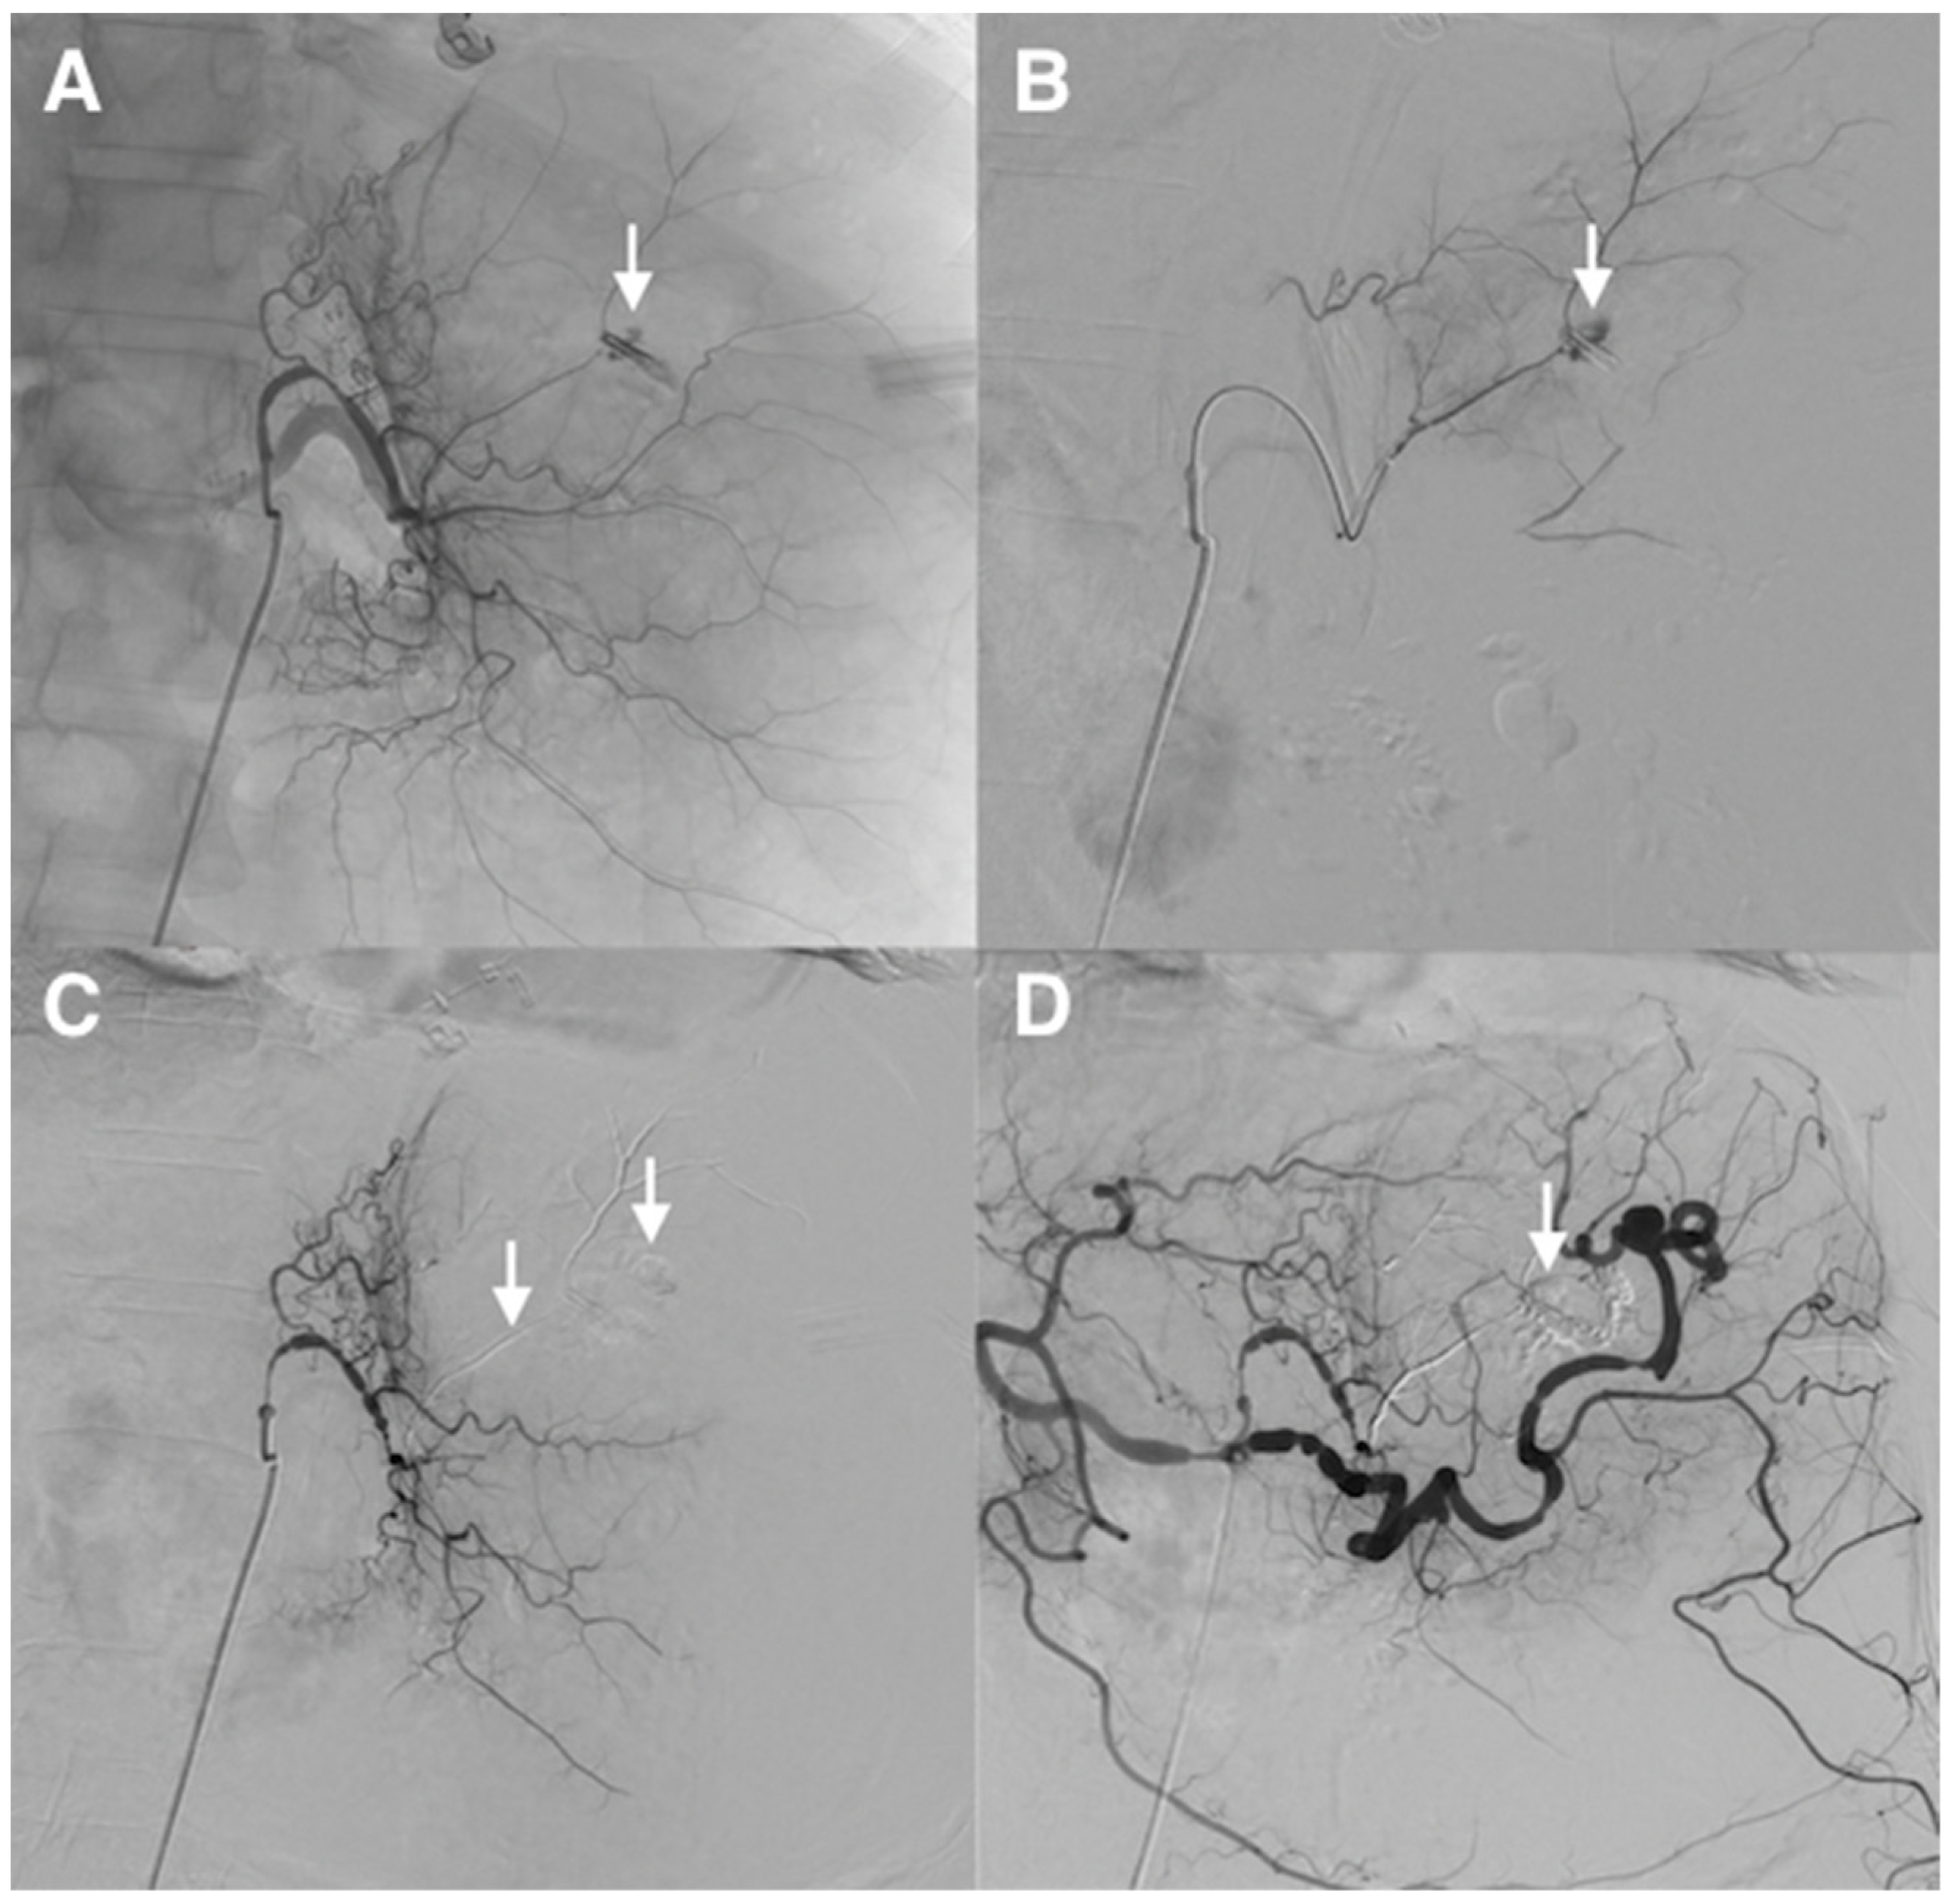

Figure 7. Refractory upper gastrointestinal hemorrhage from a gastric ulcer of the less curvature in a 64-year-old patient with coagulation disorders and hemodynamic instability. (A) Catheterism of the left gastric artery demonstrated extravasation of contrast medium from a small feeding branch of the less curvature (arrow). (B) Superselective angiogram of the bleeding artery, guided by an endoscopic metallic clip, confirmed active bleeding (arrow). (C) After selective microcatheterism, hemorrhage was controlled after superselective embolization of the feeding artery using a MagicGlue®/Lipiodol® mixture (1:3 ratio) (arrows). (D) Final control angiography showed successful superselective occlusion of the bleeding arterial branch, respecting collaterals (arrow). The patient stopped to bleed immediately.